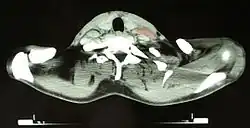

Вследствие того, что часто поражается лимфатическая ткань, расположенная в грудной клетке, первым симптомом заболевания может быть затруднение дыхания или кашель вследствие давления на лёгкие и бронхи увеличенных лимфатических узлов, но чаще всего поражение средостения обнаруживается при случайной обзорной рентгенографии грудной клетки.

- Увеличение лимфатических узлов средостения наблюдается в 45 % случаев I—II стадии. В большинстве случаев не сказывается на клинике и прогнозе, но может вызывать сдавливание соседних органов. О значительном увеличении можно говорить, когда ширина новообразования на рентгенограмме превышает 0,3 (МТИ > 3 Mass Thorac Index) по отношению к ширине грудной клетки.

Основным критерием для постановки диагноза служит обнаружение гигантских клеток Рид — Березовского — Штернберга и/или клеток Ходжкина в биоптате, извлечённом из лимфатических узлов. Используются и современные медицинские методы: (ультразвуковое исследование органов брюшной полости, компьютерная рентгеновская или магнитно-резонансная томография органов грудной клетки). При выявлении изменений в лимфатических узлах необходима гистологическая верификация диагноза.

- Компьютерная томография, ПЭТ/КТ.